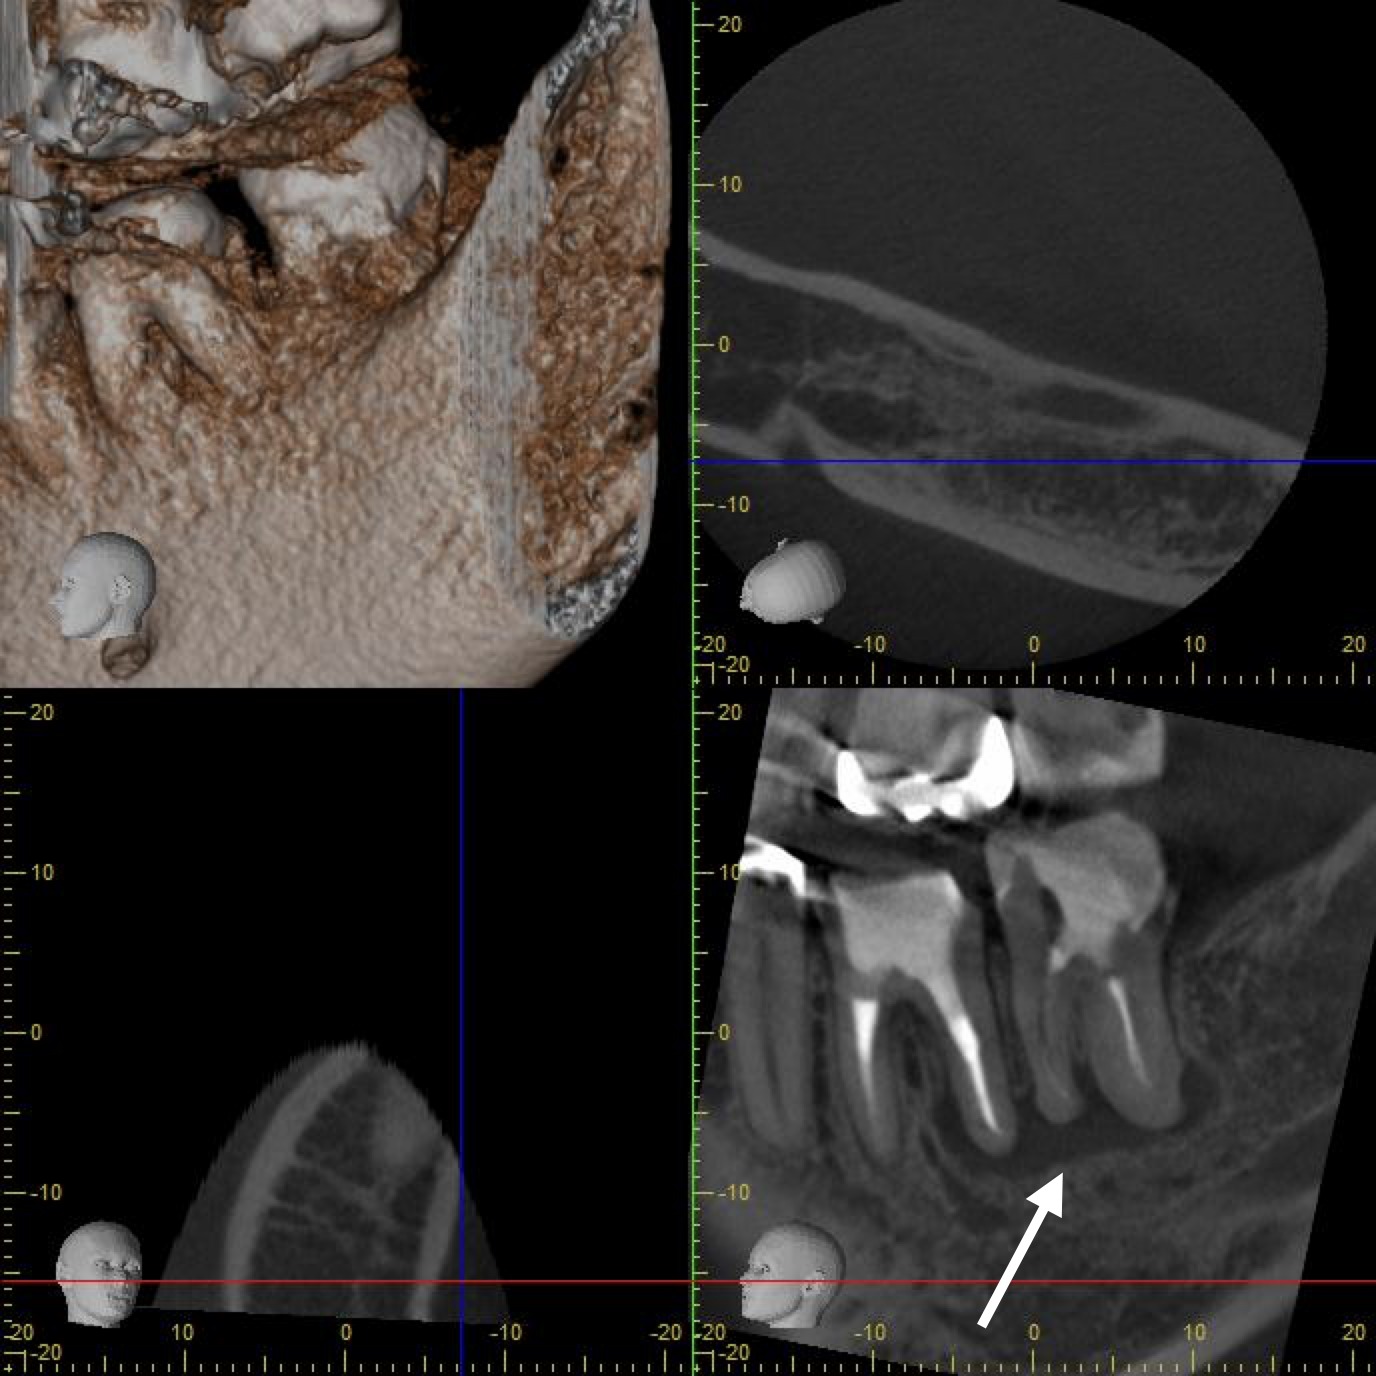

初診時の左下67番のレントゲン写真です。

左下6番に膿の出口であるサイナストラクトを認め、左下6番遠心根〜左下7番に巨大な透過像を認めます。

透過像は7番を中心に形成されているように見えますが、サイナストラクトが6番に出現していたため左下6番を原因歯と判断し精密根管治療を開始いたしました。